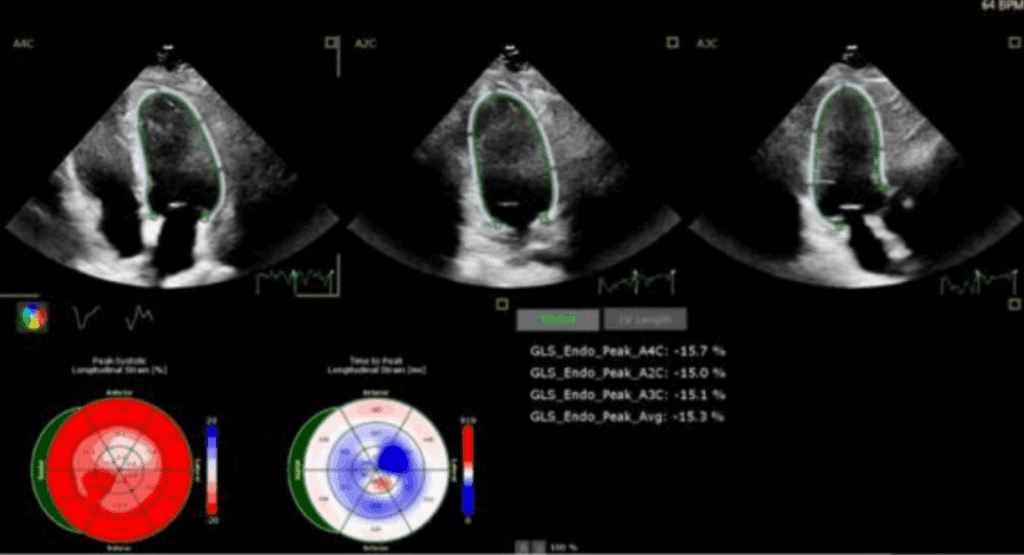

Odkształcenie mięśnia sercowego (strain) jest metodą szeroko wykorzystywaną w diagnostyce echokardiograficznej w grupie chorych z przerostem mięśnia lewej komory serca (ang. left ventricular – LV) o różnej etiologii. W tej grupie chorych standardowe przezklatkowe badanie echokardiograficzne (ang. transthoracic echocardiography – TTE) rozszerzone o pomiar odkształcenia lewej komory serca (ang. left ventricular strain – LV-GLS) ułatwia rozpoznanie, jak i pozwala na różnicowanie przyczyn przerostu LV.

W artykule przedstawiono przypadki kliniczne różnych pacjentów z chorobami układu sercowo-naczyniowego oraz przerostem mięśnia sercowego, u których pomiar odkształcenia (strain) LV istotnie ułatwia diagnostykę różnicową.